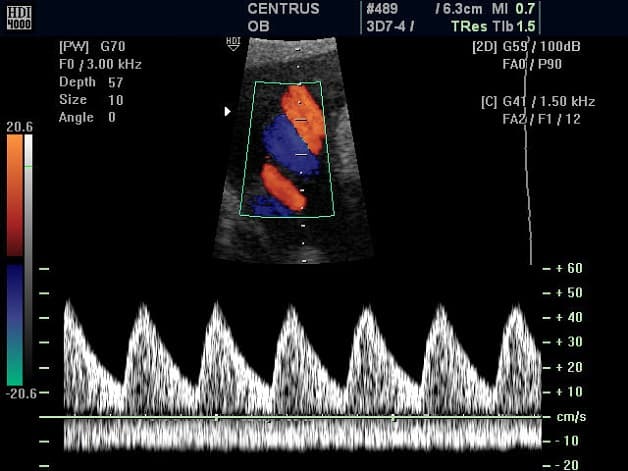

– Siêu âm doppler xung: chỉ sử dụng duy nhất một tinh thể thực hiện cả hai nhiệm vụ phát sóng và thu sóng. Với loại siêu âm này, sóng âm xuất phát từ chuỗi xung, chạy dọc theo hướng đầu dò quét. Kích thước và độ sâu của vùng lấy mẫu được bác sĩ điều chỉnh trực tiếp trên máy.

5.2 Siêu âm động mạch rốn

Bác sĩ thường tiến hành siêu âm động mạch rốn để kiểm tra lưu lượng máu ở bộ phận này bởi dây rốn có vai trò quan trọng trong việc cung cấp oxy và chất dinh dưỡng nuôi em bé trong bụng. Siêu âm này có thể được thực hiện nhiều lần trước khi sinh, thường từ tuần 34 để kiểm tra sức khỏe thai nhi và xác định tốt nhất để mẹ sinh em bé.

Khi siêu âm Doppler động mạch rốn thai nhi mà phát hiện được bất cứ vấn đề bất thường nào, bác sỹ có thể yêu cầu thêm siêu âm doppler não bộ và động mạch chủ để cho ra kết quả chính xác nhất.